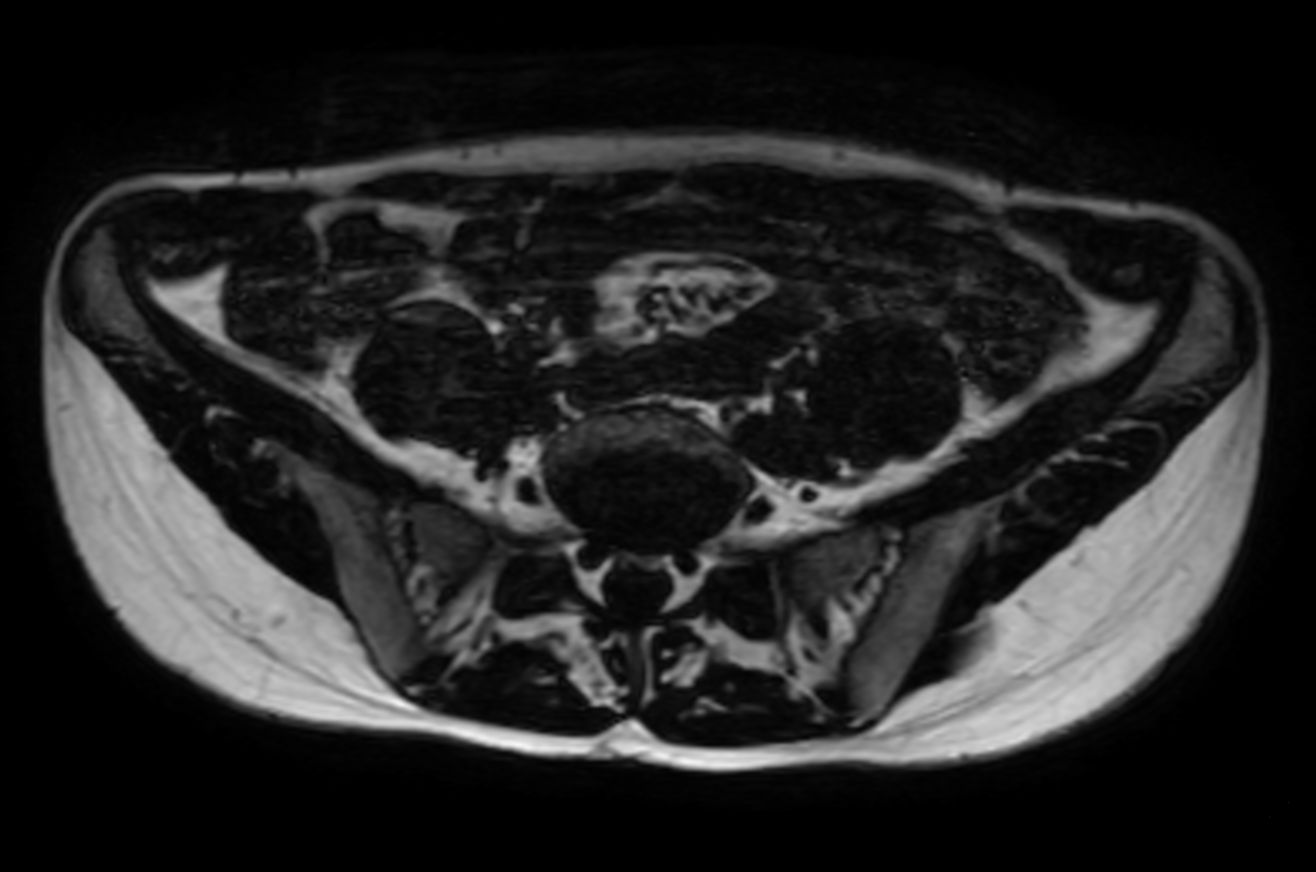

Lumbar Plexus imaging

• Clinical Application